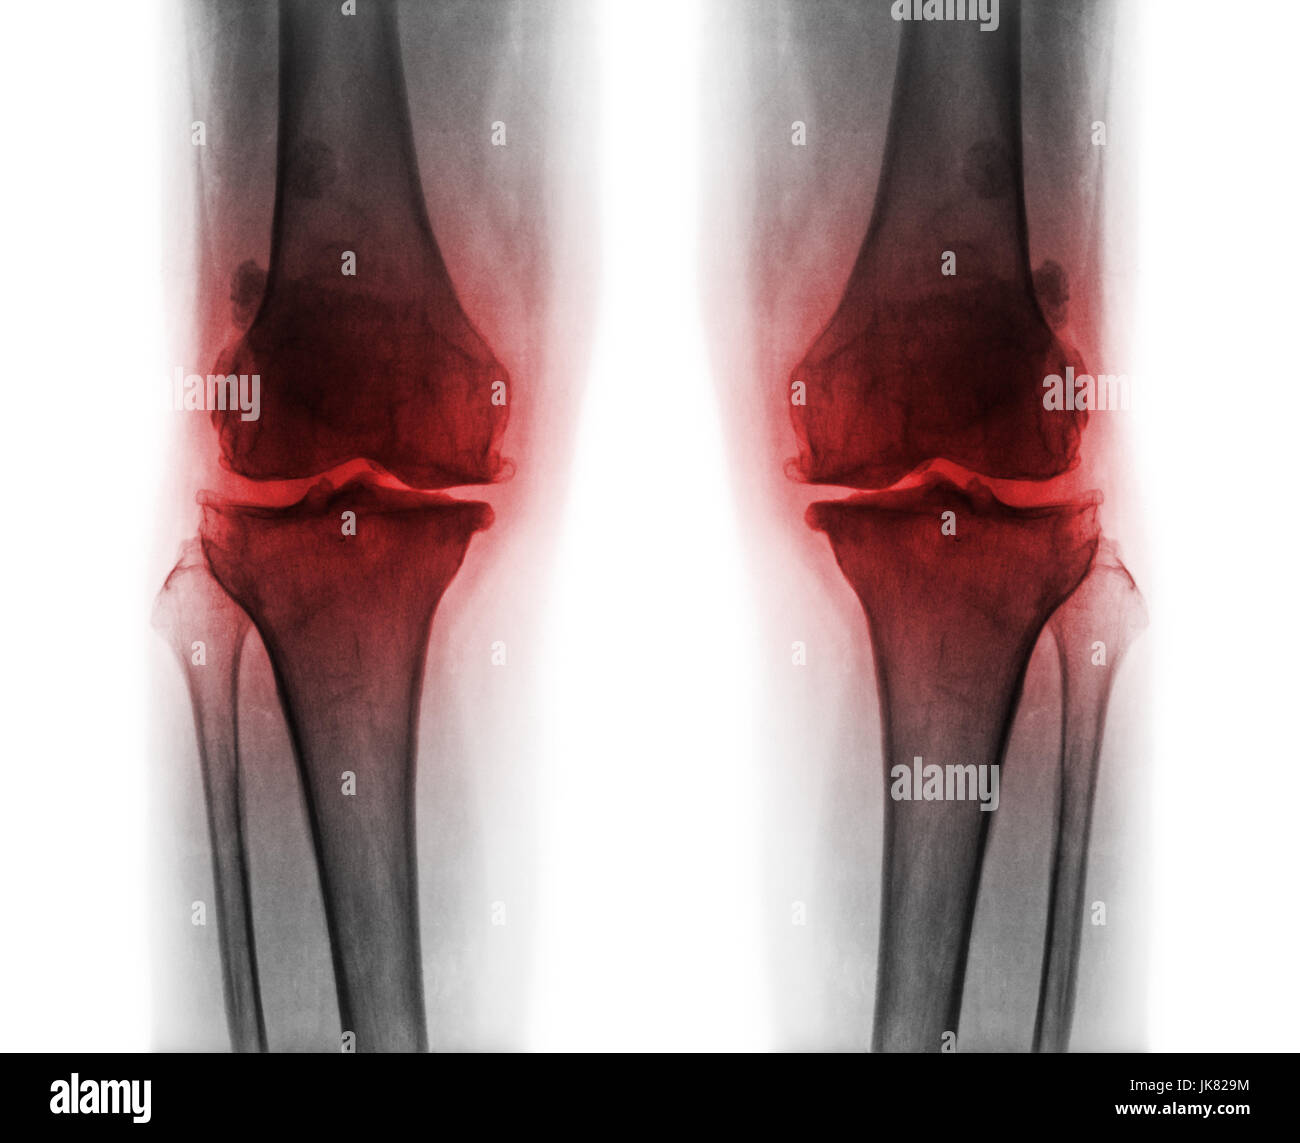

L'arthrose du genou les . film x-ray ( AP ) postérieure antérieure - de montrer l'espace commun du genou étroit éperon ( ostéophyte . ) . subcondral la sclérose en plaques . Banque D'Imageshttps://www.alamyimages.fr/image-license-details/?v=1https://www.alamyimages.fr/photo-image-l-arthrose-du-genou-les-film-x-ray-ap-posterieure-anterieure-de-montrer-l-espace-commun-du-genou-etroit-eperon-osteophyte-subcondral-la-sclerose-en-plaques-149538858.html

L'arthrose du genou les . film x-ray ( AP ) postérieure antérieure - de montrer l'espace commun du genou étroit éperon ( ostéophyte . ) . subcondral la sclérose en plaques . Banque D'Imageshttps://www.alamyimages.fr/image-license-details/?v=1https://www.alamyimages.fr/photo-image-l-arthrose-du-genou-les-film-x-ray-ap-posterieure-anterieure-de-montrer-l-espace-commun-du-genou-etroit-eperon-osteophyte-subcondral-la-sclerose-en-plaques-149538858.htmlRFJK829E–L'arthrose du genou les . film x-ray ( AP ) postérieure antérieure - de montrer l'espace commun du genou étroit éperon ( ostéophyte . ) . subcondral la sclérose en plaques .

L'arthrose du genou les . film x-ray ( AP ) postérieure antérieure - de montrer l'espace commun du genou étroit éperon ( ostéophyte . ) . subcondral la sclérose en plaques . Banque D'Imageshttps://www.alamyimages.fr/image-license-details/?v=1https://www.alamyimages.fr/photo-image-l-arthrose-du-genou-les-film-x-ray-ap-posterieure-anterieure-de-montrer-l-espace-commun-du-genou-etroit-eperon-osteophyte-subcondral-la-sclerose-en-plaques-149538864.html

L'arthrose du genou les . film x-ray ( AP ) postérieure antérieure - de montrer l'espace commun du genou étroit éperon ( ostéophyte . ) . subcondral la sclérose en plaques . Banque D'Imageshttps://www.alamyimages.fr/image-license-details/?v=1https://www.alamyimages.fr/photo-image-l-arthrose-du-genou-les-film-x-ray-ap-posterieure-anterieure-de-montrer-l-espace-commun-du-genou-etroit-eperon-osteophyte-subcondral-la-sclerose-en-plaques-149538864.htmlRFJK829M–L'arthrose du genou les . film x-ray ( AP ) postérieure antérieure - de montrer l'espace commun du genou étroit éperon ( ostéophyte . ) . subcondral la sclérose en plaques .

L'arthrose du genou les . film x-ray ( AP ) postérieure antérieure - de montrer l'espace commun du genou étroit éperon ( ostéophyte . ) . subcondral la sclérose en plaques . Banque D'Imageshttps://www.alamyimages.fr/image-license-details/?v=1https://www.alamyimages.fr/photo-image-l-arthrose-du-genou-les-film-x-ray-ap-posterieure-anterieure-de-montrer-l-espace-commun-du-genou-etroit-eperon-osteophyte-subcondral-la-sclerose-en-plaques-149538862.html

L'arthrose du genou les . film x-ray ( AP ) postérieure antérieure - de montrer l'espace commun du genou étroit éperon ( ostéophyte . ) . subcondral la sclérose en plaques . Banque D'Imageshttps://www.alamyimages.fr/image-license-details/?v=1https://www.alamyimages.fr/photo-image-l-arthrose-du-genou-les-film-x-ray-ap-posterieure-anterieure-de-montrer-l-espace-commun-du-genou-etroit-eperon-osteophyte-subcondral-la-sclerose-en-plaques-149538862.htmlRFJK829J–L'arthrose du genou les . film x-ray ( AP ) postérieure antérieure - de montrer l'espace commun du genou étroit éperon ( ostéophyte . ) . subcondral la sclérose en plaques .

L'arthrose du genou les . film x-ray ( AP ) postérieure antérieure - de montrer l'espace commun du genou étroit éperon ( ostéophyte . ) . subcondral la sclérose en plaques . Banque D'Imageshttps://www.alamyimages.fr/image-license-details/?v=1https://www.alamyimages.fr/photo-image-l-arthrose-du-genou-les-film-x-ray-ap-posterieure-anterieure-de-montrer-l-espace-commun-du-genou-etroit-eperon-osteophyte-subcondral-la-sclerose-en-plaques-149538859.html

L'arthrose du genou les . film x-ray ( AP ) postérieure antérieure - de montrer l'espace commun du genou étroit éperon ( ostéophyte . ) . subcondral la sclérose en plaques . Banque D'Imageshttps://www.alamyimages.fr/image-license-details/?v=1https://www.alamyimages.fr/photo-image-l-arthrose-du-genou-les-film-x-ray-ap-posterieure-anterieure-de-montrer-l-espace-commun-du-genou-etroit-eperon-osteophyte-subcondral-la-sclerose-en-plaques-149538859.htmlRFJK829F–L'arthrose du genou les . film x-ray ( AP ) postérieure antérieure - de montrer l'espace commun du genou étroit éperon ( ostéophyte . ) . subcondral la sclérose en plaques .